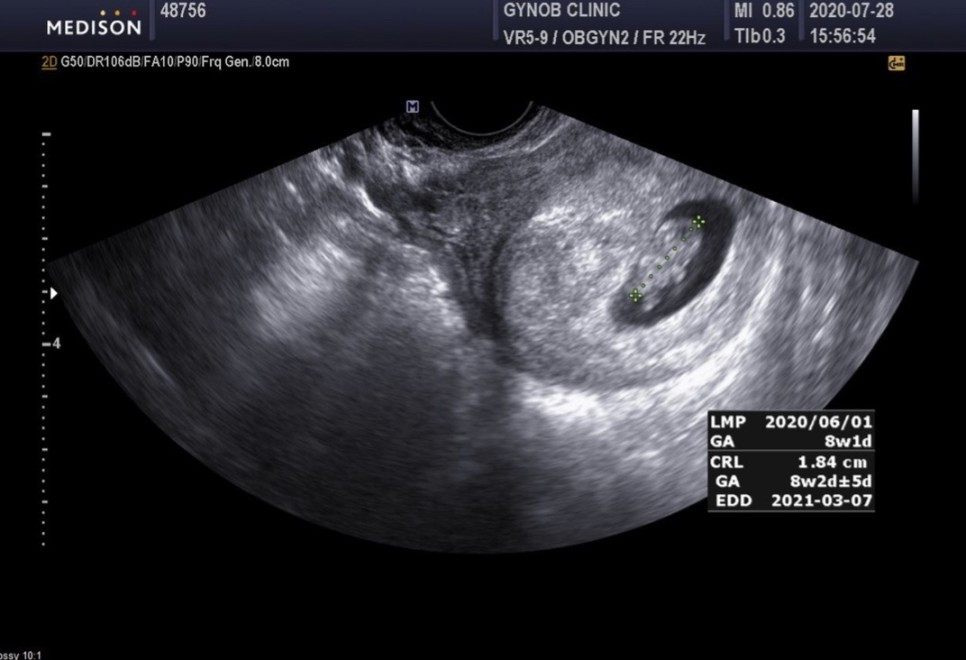

역시나! 예약이 다 찼다고 했다. '그럼 난 언제 가야하나?' 했는데, 예약은 안되지만 방문이 가능한 시간은 안내해주셨다. 예약과 예약 사이에 원장님께서 진료를 보신다고 한 것 같은데.. 정확한 시스템은 아직 모르겠다. 오게 되면 대기하고 기다렸다가 진료를 받으면 된다고 알려주셨다. 뭔가 참 귀찮게 느껴지기도 했지만 일단 가보기로 했으니! 2주만에 다시 찾아온 새로운 산부인과. 처음 오는 병원이다보니 왠지 더 긴장이 됐다. 지난번 초음파로 봤을 때 임신주수 5주 4일차 정도 된다고 하셨고, 딱 2주 뒤니 7주 4일차쯤 되지 않을까 생각하고 있었다. 하지만 내 예상을 넘어서 8주 1일이 나왔다. 2주간 부쩍 입덧과 속쓰림이 심해져서 힘든 일상을 보냈는데, 그래도 아가가 잘 크고 있었다~!! 5주에서 8주 사이 유산이 가장 많다고 어디서 본 것 같았는데.. 8주가 넘어서서 한결 마음이 놓였다.

3번째 초음파. 2주전 5mm였던 아가가 1.84cm가 되었다.(지금은 더 컸겠지^^)

아가의 심장박동은 171로 아주아주 잘 뛰고 있지만 그래도 아직까지 우려되는 피고임..

선생님께서 1-2주 정도 흡수가 되는지를 지켜본다고 하셨다. 어쨌든 생각보다 꽤 오래가는 것 같아 잠깐씩 또 불안불안 하다. 혹시 흡수가 안되면 무슨일이 생기는건지.. 많이들 경험하는 사례라고 하나 결코 안심해도 되는 상황은 아니라고 한다. 그래도 아직까지 다행이라 생각하는 것은 임신하고 단 한번도 피가 몸 밖으로 보였던 적은 없었다. 배란혈 때문에 그렇게 걱정을 한 것 치고는!! 초기에는 꽤 부정출혈이 흔하다고 하는데 난 아직까지 단 한번도 없음.